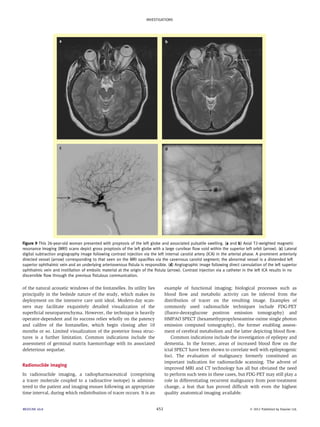

Figure 9 This 26-year-old woman presented with proptosis of the left globe and associated pulsatile swelling. (a and b) Axial T2-weighted magnetic

resonance imaging (MRI) scans depict gross proptosis of the left globe with a large curvilear flow void within the superior left orbit (arrow). (c) Lateral

digital subtraction angiography image following contrast injection via the left internal carotid artery (ICA) in the arterial phase. A prominent anteriorly

directed vessel (arrow) corresponding to that seen on the MRI opacifies via the cavernous carotid segment; the abnormal vessel is a distended left

superior ophthalmic vein and an underlying arteriovenous fistula is responsible. (d) Angiographic image following direct cannulation of the left superior

ophthalmic vein and instillation of embolic material at the origin of the fistula (arrow). Contrast injection via a catheter in the left ICA results in no

discernible flow through the previous fistulous communication.